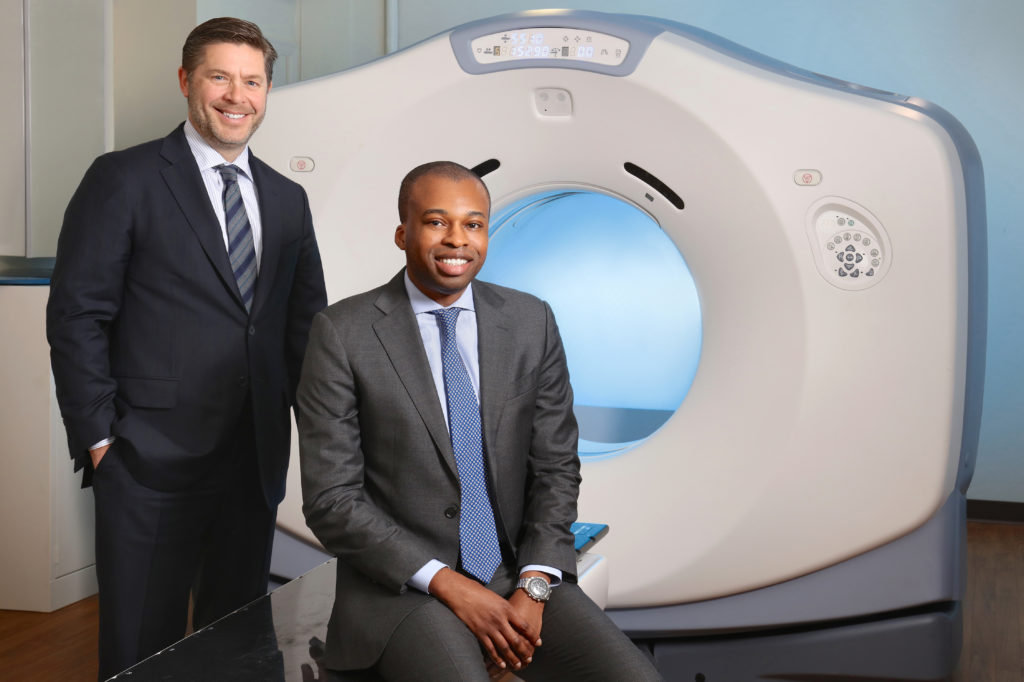

Dr. Sibley and Dr. Agbahiwe- Virginia Cancer Specialists